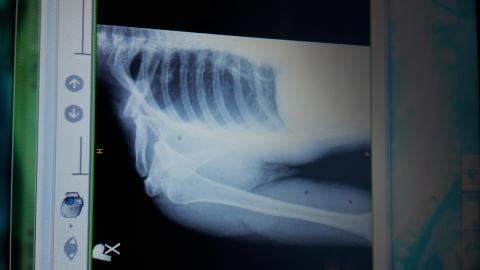

Zlomenina

Pro větší náhled klikněte na obrázek

Dobry vecer,chcel by som sa spytat ci sa da zoperovat zle zrastena zlomenina claviculy? Som uz vyse 2mesiacov po zlomenine a mi to pomerne vadi a k tomu mi trpnu prsty da sa po takej dlhsej dobe operovat znova lamat a drotovat?

Dobrý den, i taková možnost tu existuje, bohužel její výsledky nemusí být dobré, není to jako u čerstvé zlomeniny. Divím se, že takovou zlomeninu vám neoperovali a nechali jen srůst. Zkusila bych ještě rehabilitace na uvolnění pohybů a vitamin B k posílení regenerace nervu.